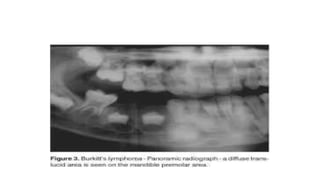

Radiographic findings

• ill-defined radiolucency

• Loss of lamina dura and developmental crypt(s) around erupted and

unerupted teeth

• Uniform widening of periodontal membrane space(garrington’s sign)

• Teeth may be displaced, causing malocclusion and/or

exfoliation.(Dental Anarchy)

• Root truncation